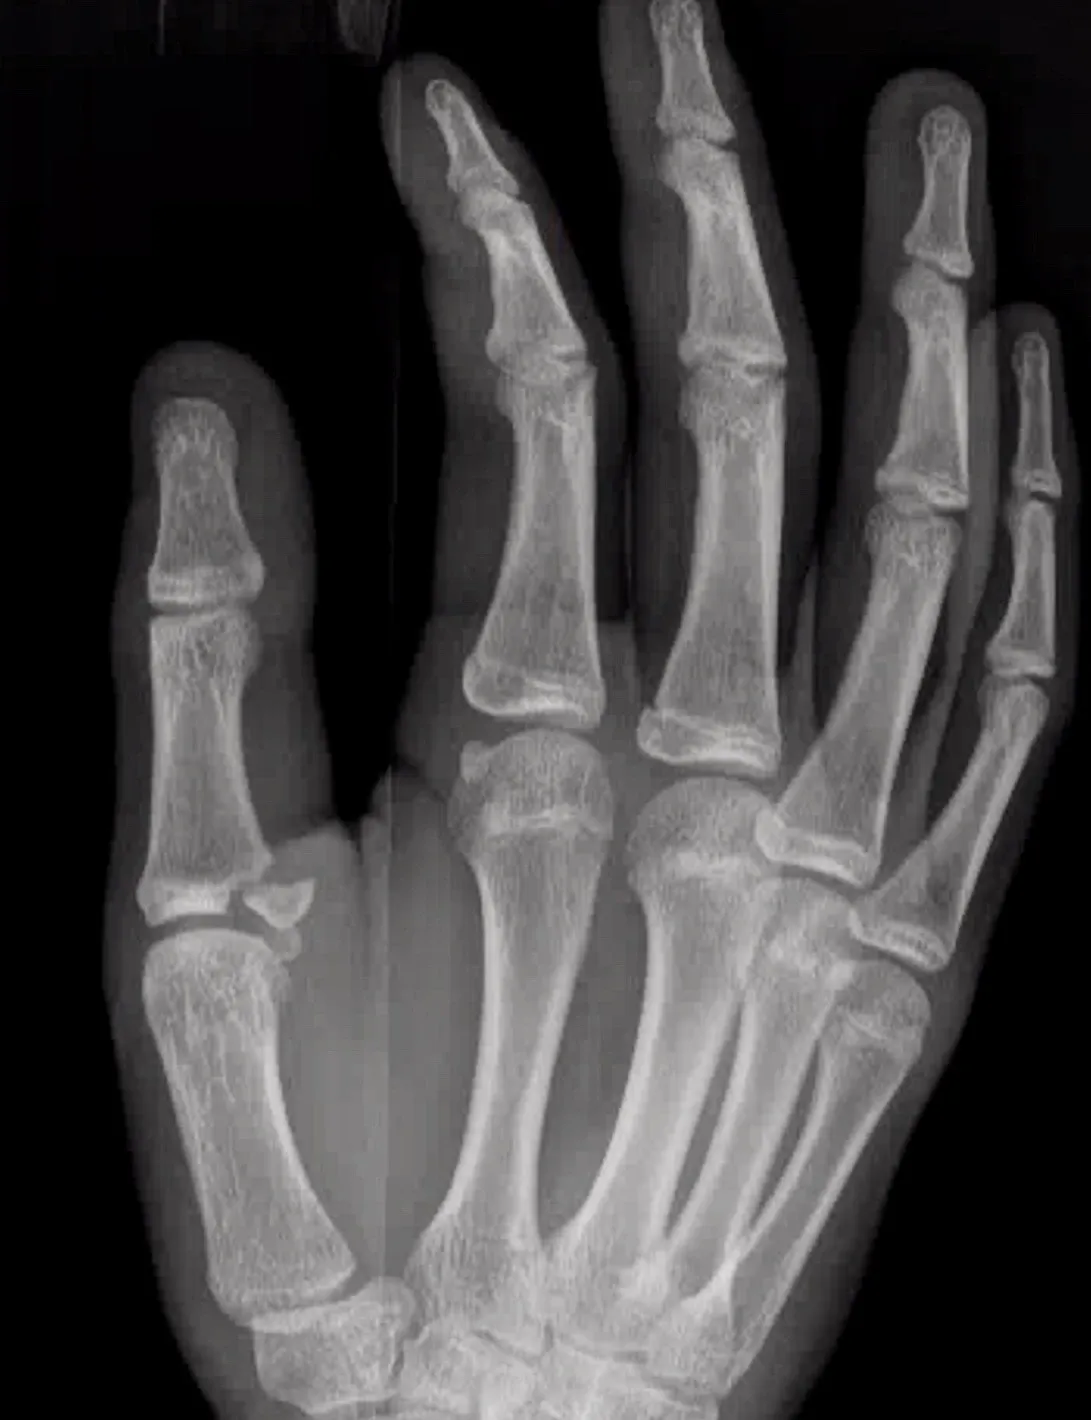

Vingerartrose

Wat is het?

Bij vingerartrose slijt het kraakbeen van de hand- en vingergewrichten, meestal aan de eindkootjes (DIP), maar soms ook aan PIP- en MCP-gewrichten. Oorzaken kunnen zijn: vroegere letsels, overbelasting, doorgemaakte infectie, reumatische ziekten of erfelijke aanleg.

Chirurgisch

- Bij blijvende pijnklachten:

- Artrodese (het gewricht vastzetten)

- Prothese (gewrichtsvervanging)

Welke ingreep geschikt is, wordt individueel besproken. Operaties gebeuren in dagziekenhuis onder plexusverdoving.